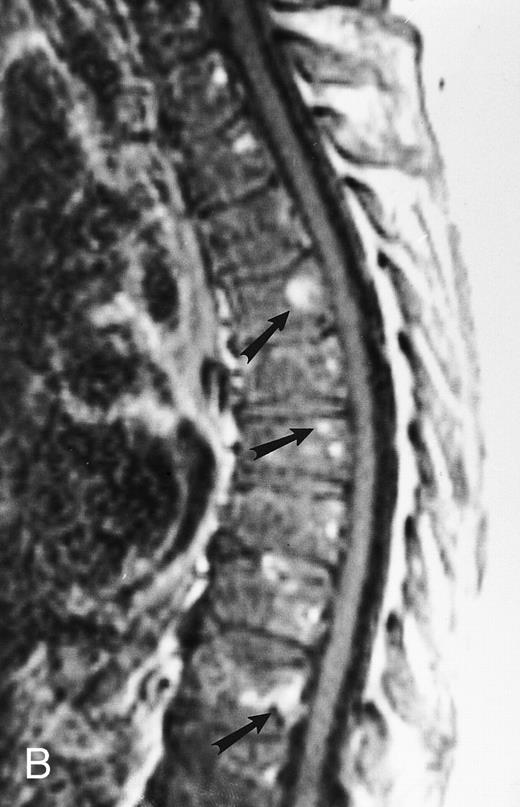

Diffuse MR pattern of abnormal marrow in a 29-year-old man with AML: T1-weighted sagittal (500/10, TR/TE) (A), T2-weighted, fat-suppressed fast spin echo sagittal (5000/96, TR/TE, ET 16) (B), and enhanced T1-weighted sagittal (500/10, TR/TE) (C) MR images of the thoracic spine. The abnormal vertebral bodies in (A) are dark and isointense to the intervertebral discs and in (B) they become bright. In (C), the abnormal marrow enhances and the vertebrae become brighter than the discs. Note extraosseous mass (arrowheads) in the posterior epidural space with preservation of the bony cortex.